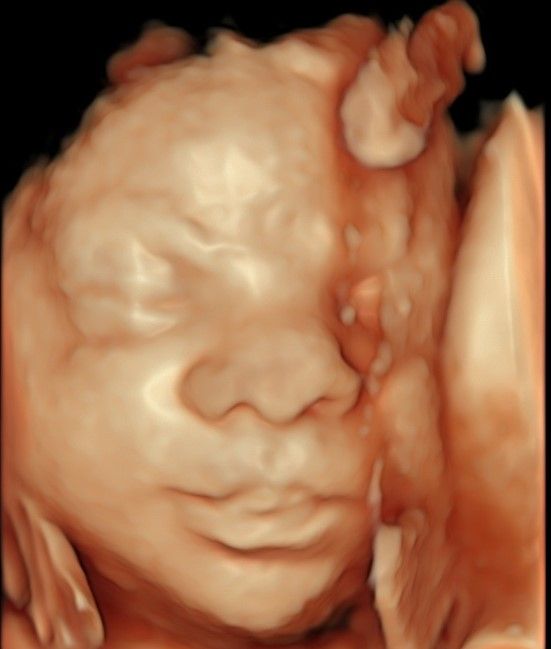

Eseguo in particolare ecografie ostetriche e ginecologiche anche in 3D e 4D per meglio identificare la problematica, offrire diagnosi precise ed un trattamento mirato e personalizzato.

• Arcispedale Santa Maria Nuova - IRCSS Reggio Emilia ecografia ostetrica 3D/4D  •